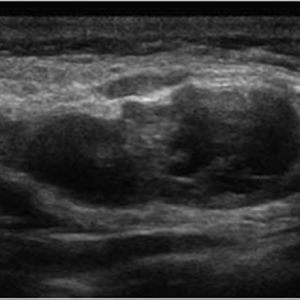

U tuyến nước bọt

Lượt xem: 167» 18-01-2021 -

U tuyến nước bọt

Lượt xem: 184» 18-01-2021 -

U tuyến nước bọt

Lượt xem: 135» 18-01-2021 -